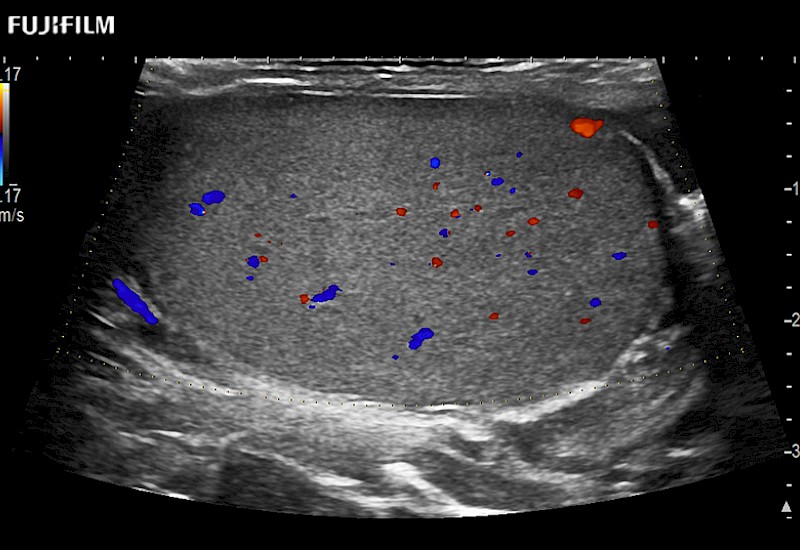

including: B-Mode, Color Doppler, Power Doppler, Fine Flow

– better visualization of tumors to improve understanding of blood flow information